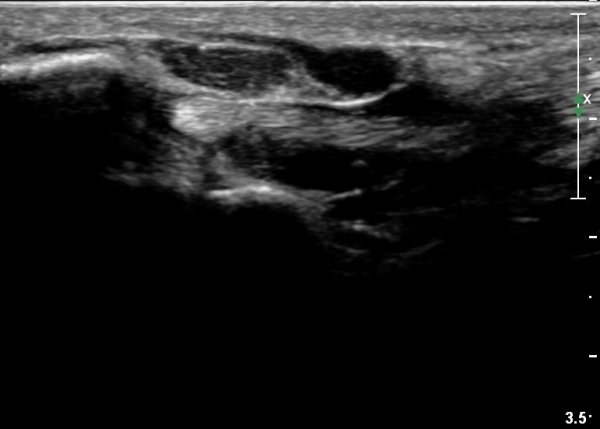

¼Õ¹Ù´Ú ±ÙÀ§ºÎ Ⱦ´Ü¸é°Ë»ç¿¡¼­ Á¤Á߽ŰæÀº ºÎÁ¾ µî ƯÀÌ ¼Ò°ßÀÌ º¸ÀÌÁö ¾ÊÀ¸³ª

¹«Áö±Ù °æ°èºÎ ̫̿¿¡ Àú¿¡ÄÚ Á¾¾çÀÌ °üÂûµÈ´Ù(»çÁø 4, 5).